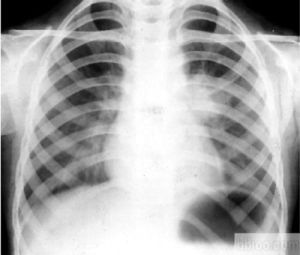

此型結核在臨床表現可輕可重,輕者可無症狀,偶可體檢時,作胸透時才被發現;重者可有結核中毒症狀,如長期低熱,輕咳,食欲不振,消瘦等,多見年齡較大兒童;再有表現為急性發病,多見於嬰幼兒,突然高熱持續2~3周,爾後低熱,但一般情況尚可,也可伴結核中毒症狀。如腫大的淋巴結壓迫氣管、支氣管,可有陣發性咳嗽或哮喘性呼吸困難。體格檢查肺部可無陽性體徵,可僅有全身淺表淋巴結腫大。血常規檢查:白細胞計數或可增加,核左移。血沉增快。痰細菌培養有時陽性。結核菌素試驗大都強陽性。X線檢查:原發綜合徵可見雙極啞鈴狀徵象;支氣管淋巴結核,可見肺門淋巴結腫大,或伴肺門炎性浸潤。